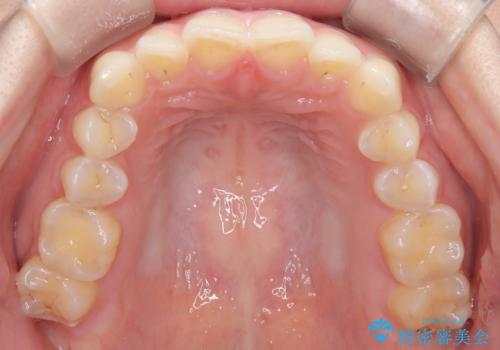

- 前歯のガタガタが気になるとのことでご相談いただきました。診察すると、歯列のスペースが不足し、前歯が重なっている状態でした。抜歯をせずに整えるため、歯と歯の間をわずかに削るIPR(歯列幅径削除)と、奥歯を後方へ動かす遠心移動を組み合わせてスペースを確保しながら並べる治療計画を立てました。

インビザラインを用いて歯を少しずつ移動させながら、IPRで微調整を行い、スペースを確保しました。また、奥歯を遠心移動させることで、前歯を自然な位置に並べることができました。治療後は、「ガタガタがなくなり、スムーズな歯並びになった」と患者様にもご満足いただきました。